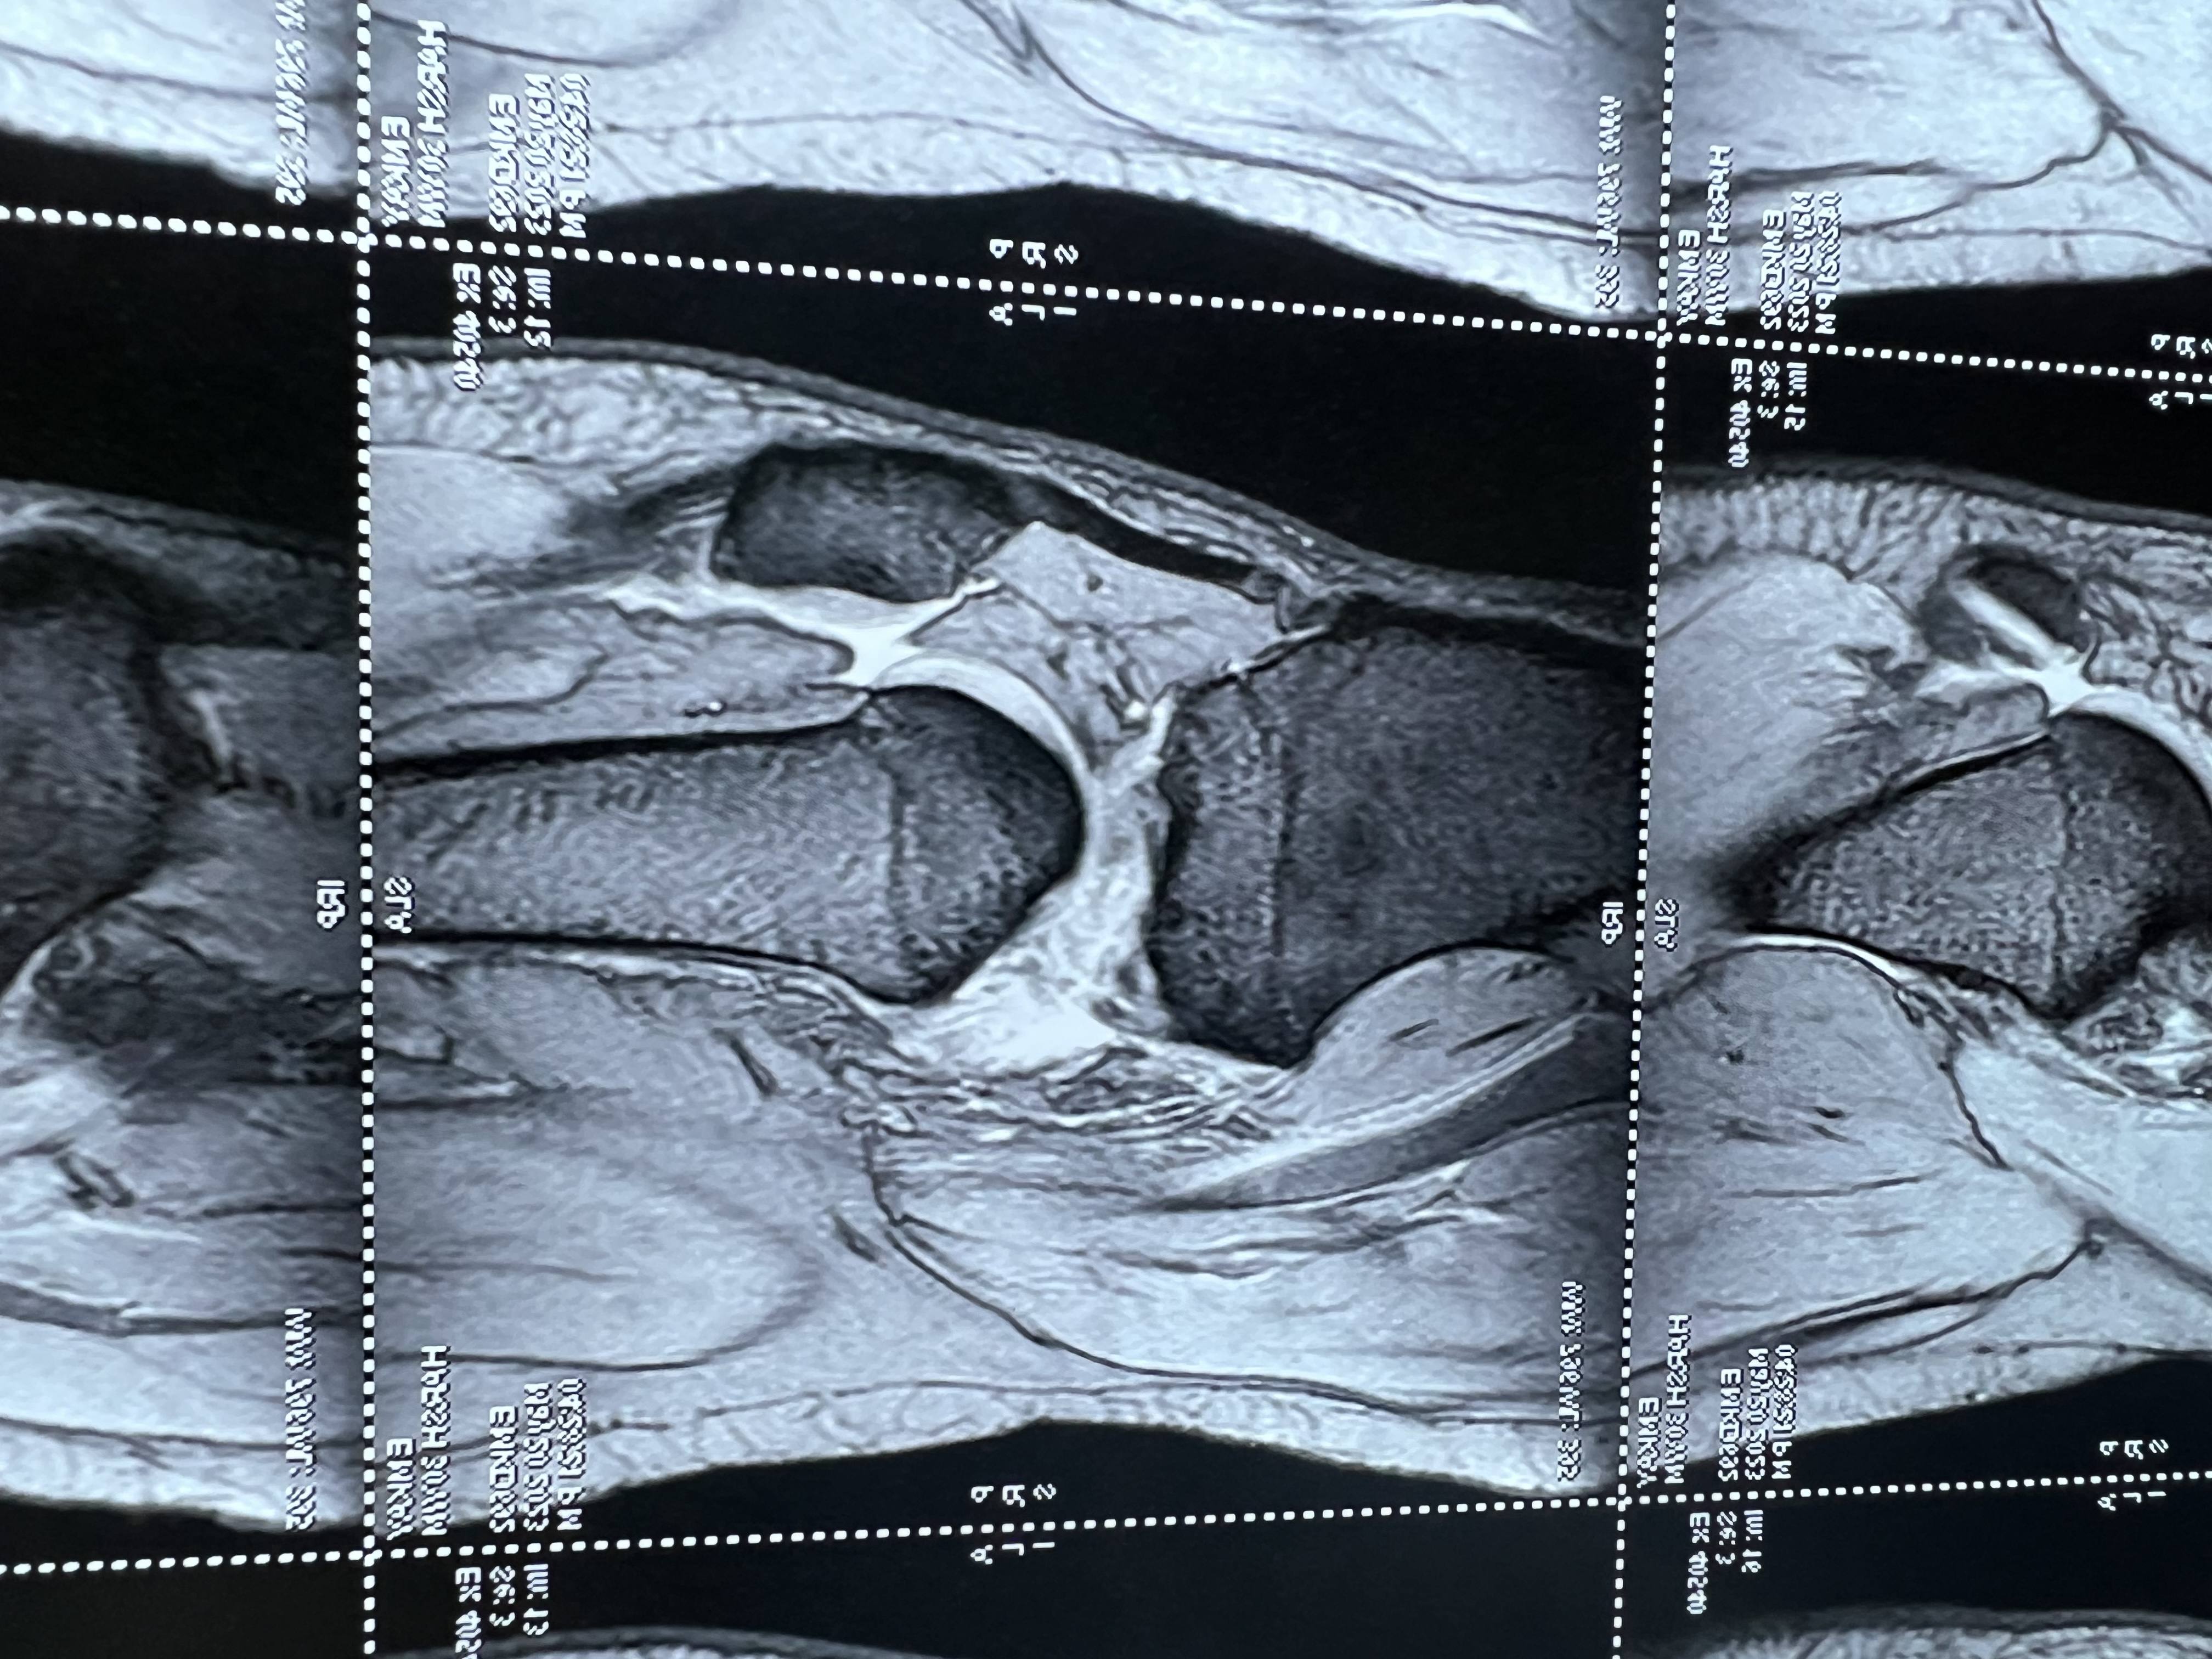

After ACL surgery, most patients can begin light jogging in about 3 months and progress to running by 6 months. However, recovery time can vary from person to person. Some patients may take longer if their thigh muscles are still weak or rehabilitation has not been adequate. If you are unable to run even after 7 months of ACL surgery, the possible reasons may include: Improper or incomplete rehabilitation exercises – Weak quadriceps and hamstring muscles can delay recovery. Loose or stretched ligament graft – This can affect knee stability and confidence while running. Failure of ACL surgery – In rare cases, the graft may not have healed properly. Associated knee problems – Meniscus or cartilage issues can also cause pain or instability. In such a situation, it is important to visit your orthopedic surgeon for a proper clinical examination. If required, your doctor may advise a 3 Tesla MRI scan to evaluate the condition of the ACL graft and bone tunnels. If the MRI shows that the graft and tunnels are normal, then focused physiotherapy and structured rehab can help you return to running. Working with a trained physiotherapist can make a big difference in regaining strength, balance, and confidence. I hope this information helps you understand the reasons and the right steps to take for a successful recovery.